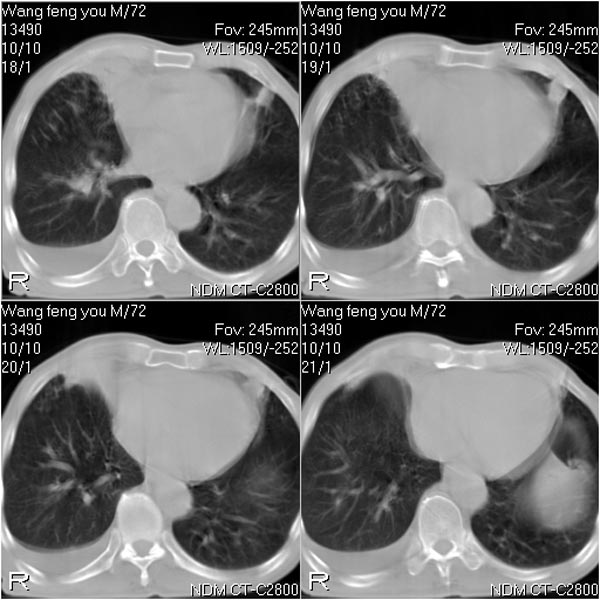

患者:男 72岁 右肩痛半年,近日来咳血,就诊.

右肺中心型肺癌并上叶不张,右侧胸腔积液,做镜检吧.

典型右中心型肺癌并右肺上叶不张,左肺转移,右胸腔积液。

考虑:右肺上叶中心型肺癌伴肺不张、肋骨转移、肩胛骨转移、右侧胸腔积液。

1.考虑:右肺上叶中央型肺癌并右肺上叶不张及右侧多发肋骨、上纵隔淋巴结及左肺转移。

2.右侧胸腔积液。